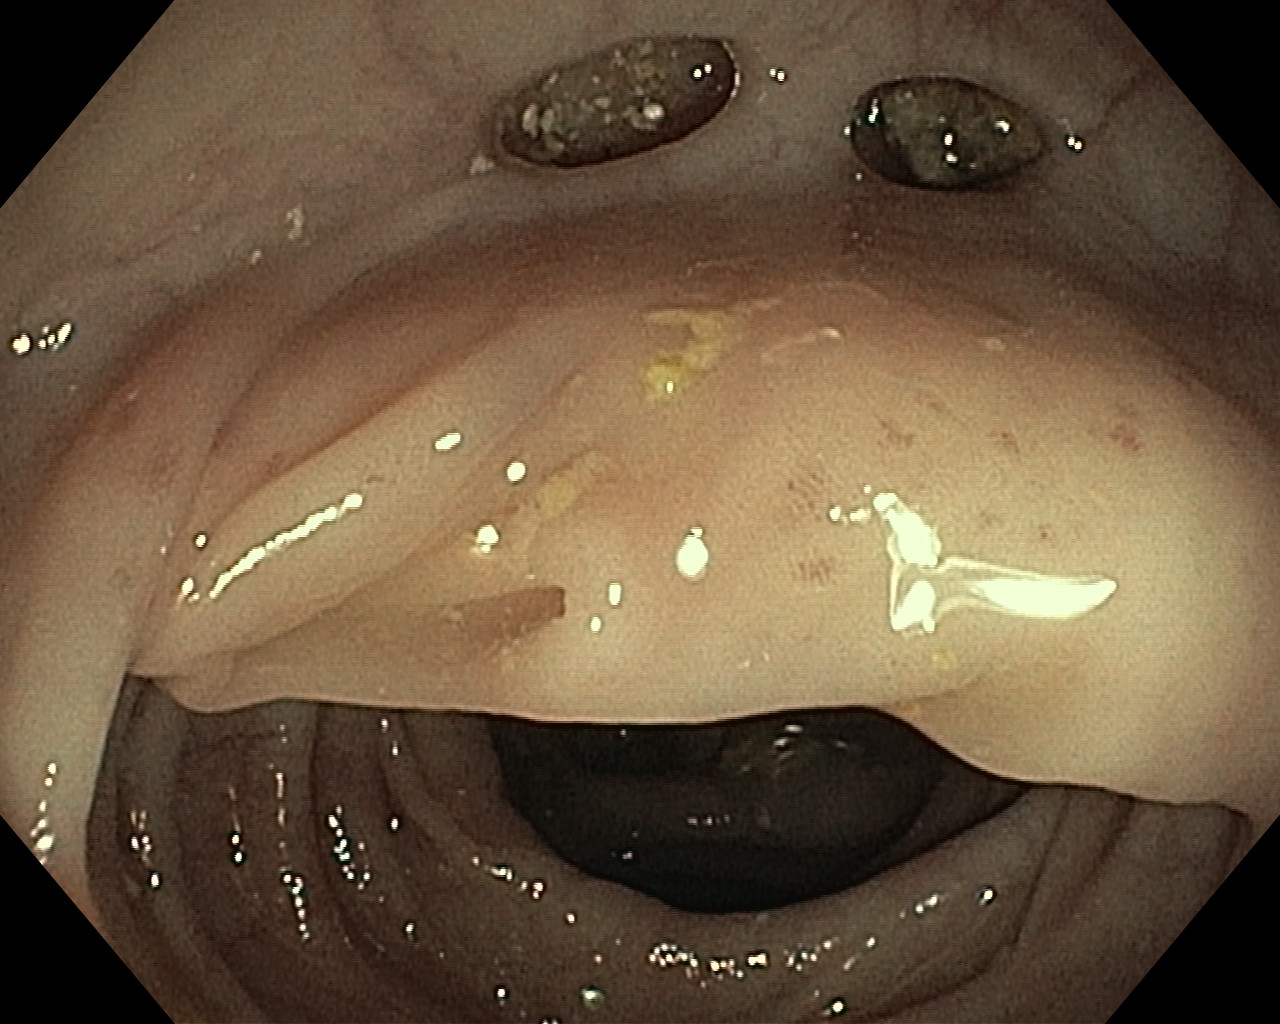

Uchyłki